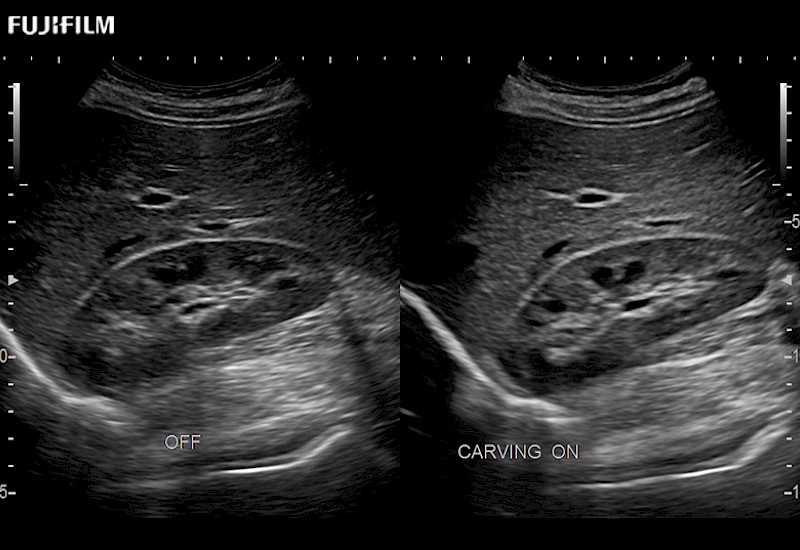

Our dedication to Laparoscopic Surgery allows us to offer superior image quality, outstanding system reliability and intuitive use of cutting edge technology.

The ARIETTA 750 incorporates all of the proven technologies and functions that medical professionals have come to expect from Fujifilm Healthcare.

ARIETTA 750 is the definitive diagnostic ultrasound solution for any clinical setting - Private Office, Imaging Center, or Hospital. The ARIETTA platform provides the ultimate in clinical performance with its state-of-the-art features and large user-friendly display.

The ARIETTA 650 DI combines trusted Fujifilm Healthcare technologies and features tailored for surgical oncology.

Designed to meet the demands of surgeons, the ARIETTA 650 DI offers precise guidance. Its advanced capabilities and large, intuitive display offer accurate and efficient care in operating rooms and specialized surgical settings.